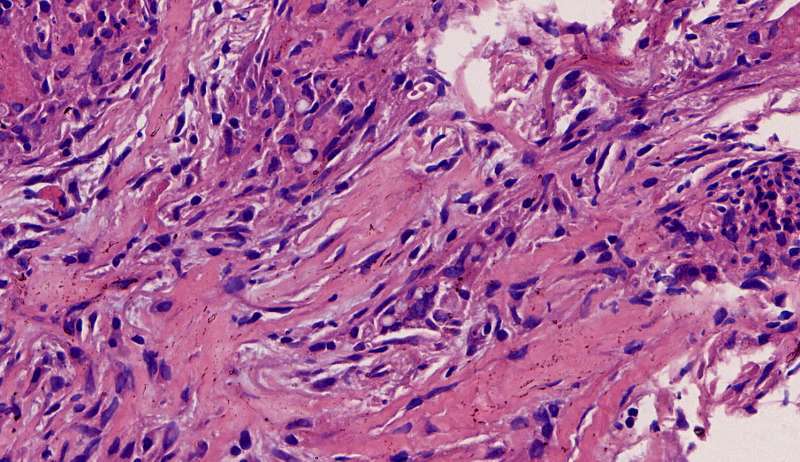

最后发一例化脓性炎症

中性粒细胞很多,此处组织结构破坏

左侧液化,脓肿壁较规则平滑

周围的炎症机化区

破坏力在这里逐渐减弱

逐渐从中性粒细胞转为淋巴细胞为主

周边区:

肺泡内有渗出,逐渐吸收 机化是不是纤维细胞增多看的?王:是的